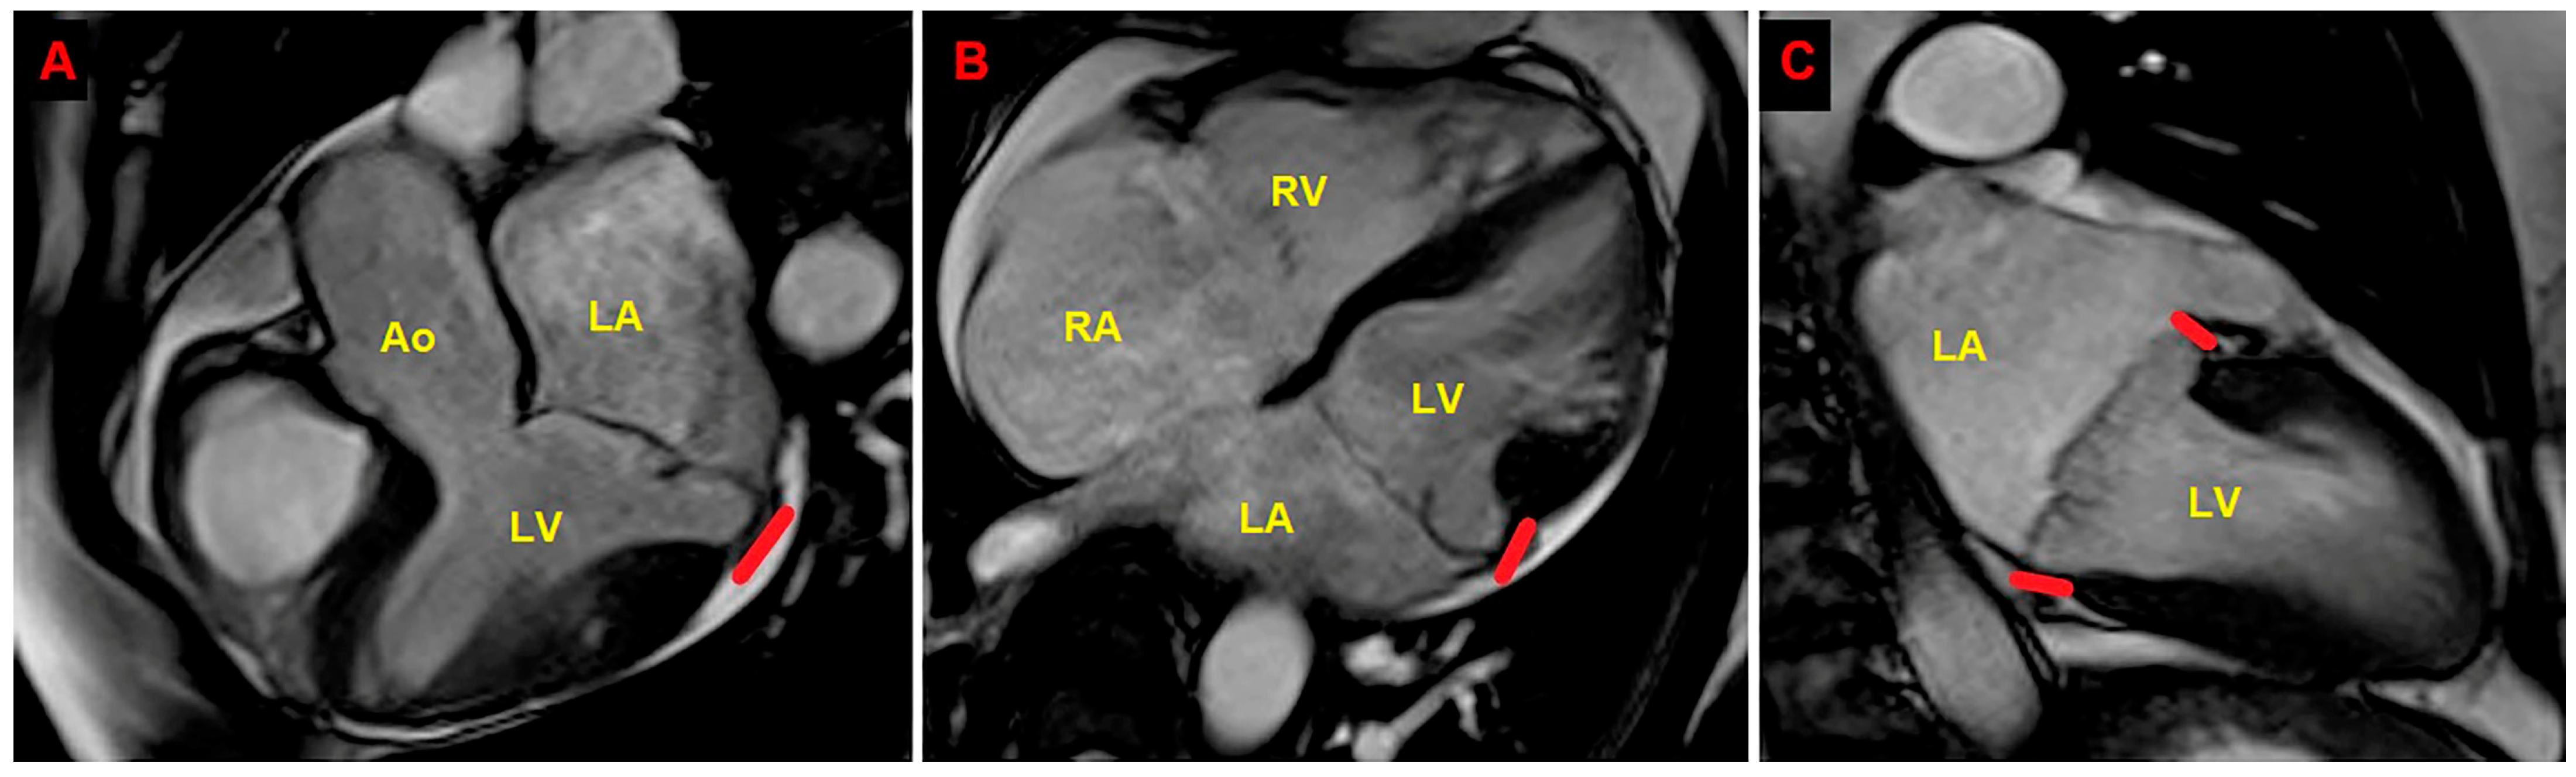

2. Clinical Case

3.1. The Role of CMR in MAD Assessment